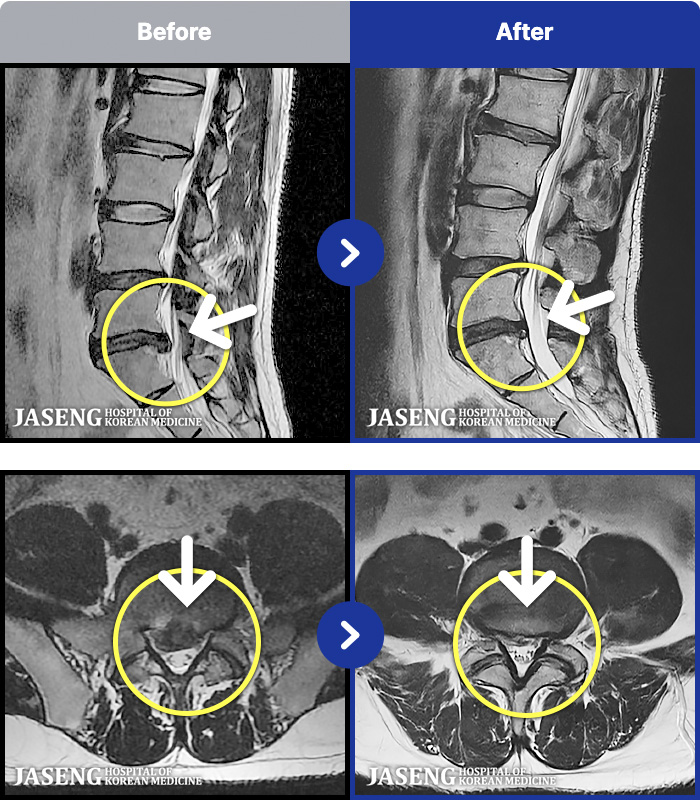

[ϻ] 24.07.25~25.08.01

ȯںп Ǹ ǿ ԿǾ, ο ġ ۿ Ƿ ġḦ Ͻñ ٶϴ.